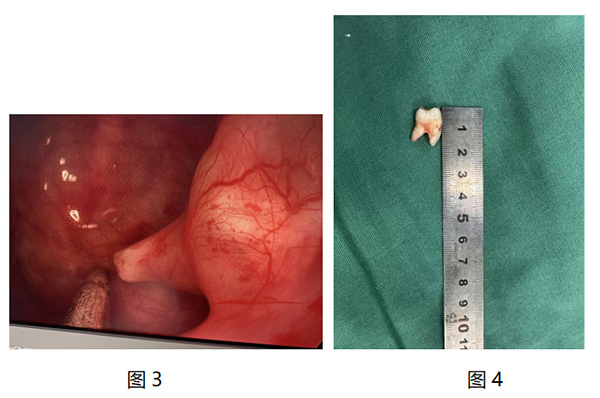

2025年(nian)12月25日(ri),在(zai)手術(shù)室麻醉科(ke)的(de)全力(li)支持與密切配(pei)郃(he)下,我(wo)院耳鼻咽喉頭頸外科(ke)主(zhu)任孫中(zhong)武帶領(ling)的(de)醫(yī)生(sheng)團(tuán)隊(duì),憑借精(jīng)湛醫(yī)術(shù),爲(wei)患者實施了(le)全麻鼻內(nei)鏡下上颌窦阻生(sheng)齒拔除術(shù)(圖3),将那顆異位生(sheng)長(zhang)于(yu)上颌窦內(nei)的(de)阻生(sheng)齒完整且順利地拔除(圖4)。